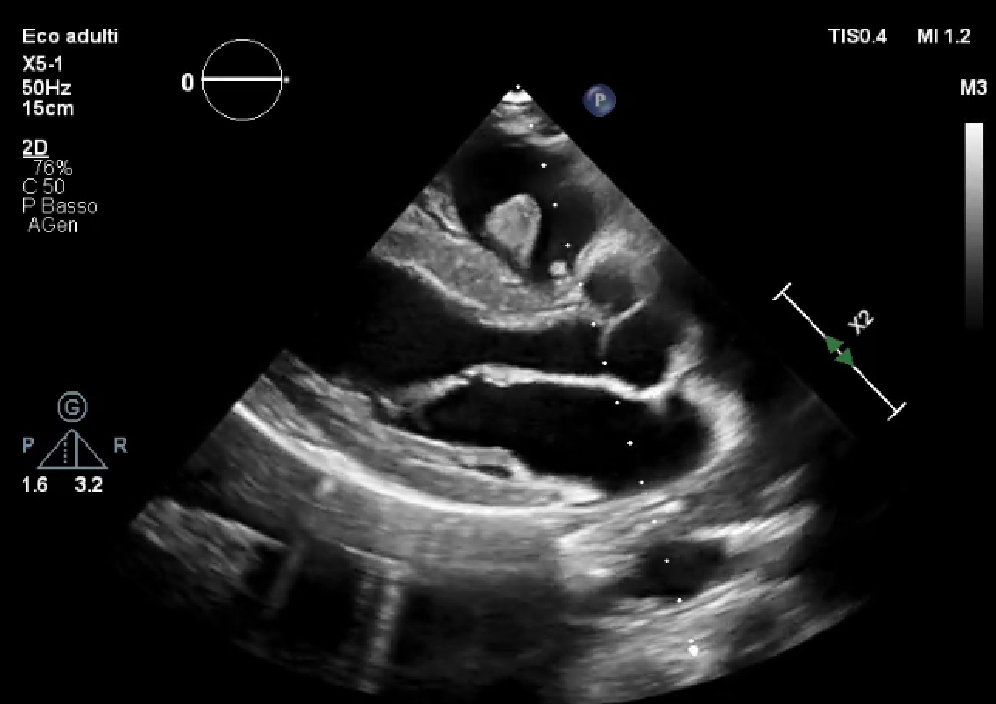

Continua la nuova edizione 2025 la rubrica SIECVI Case Study Quiz con il caso clinico della dott.ssa Paola Siena (SIECVI Puglia) selezionato dalla commissione dedicata del Settore Operativo Comunicazione per i contenuti interessanti e utili alla formazione.